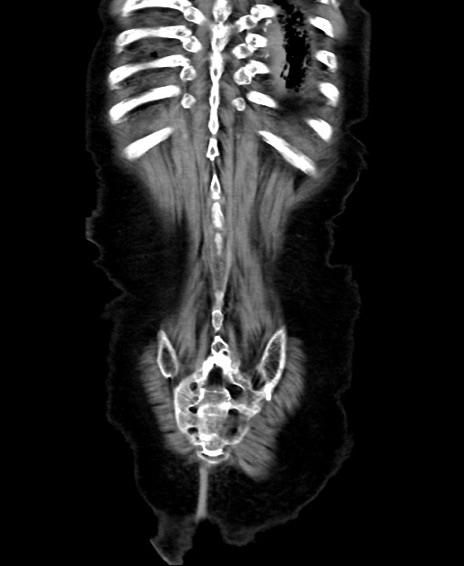

矢状断像